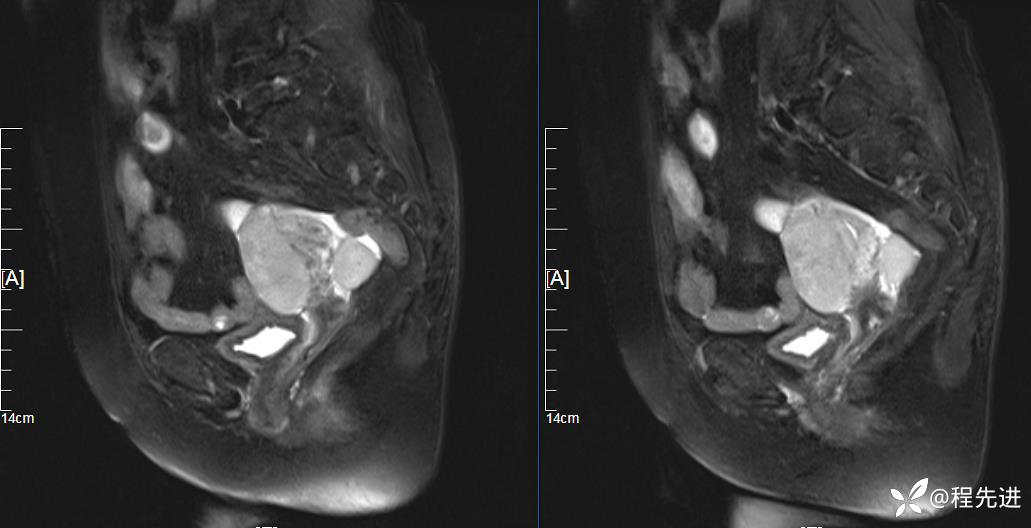

T2: